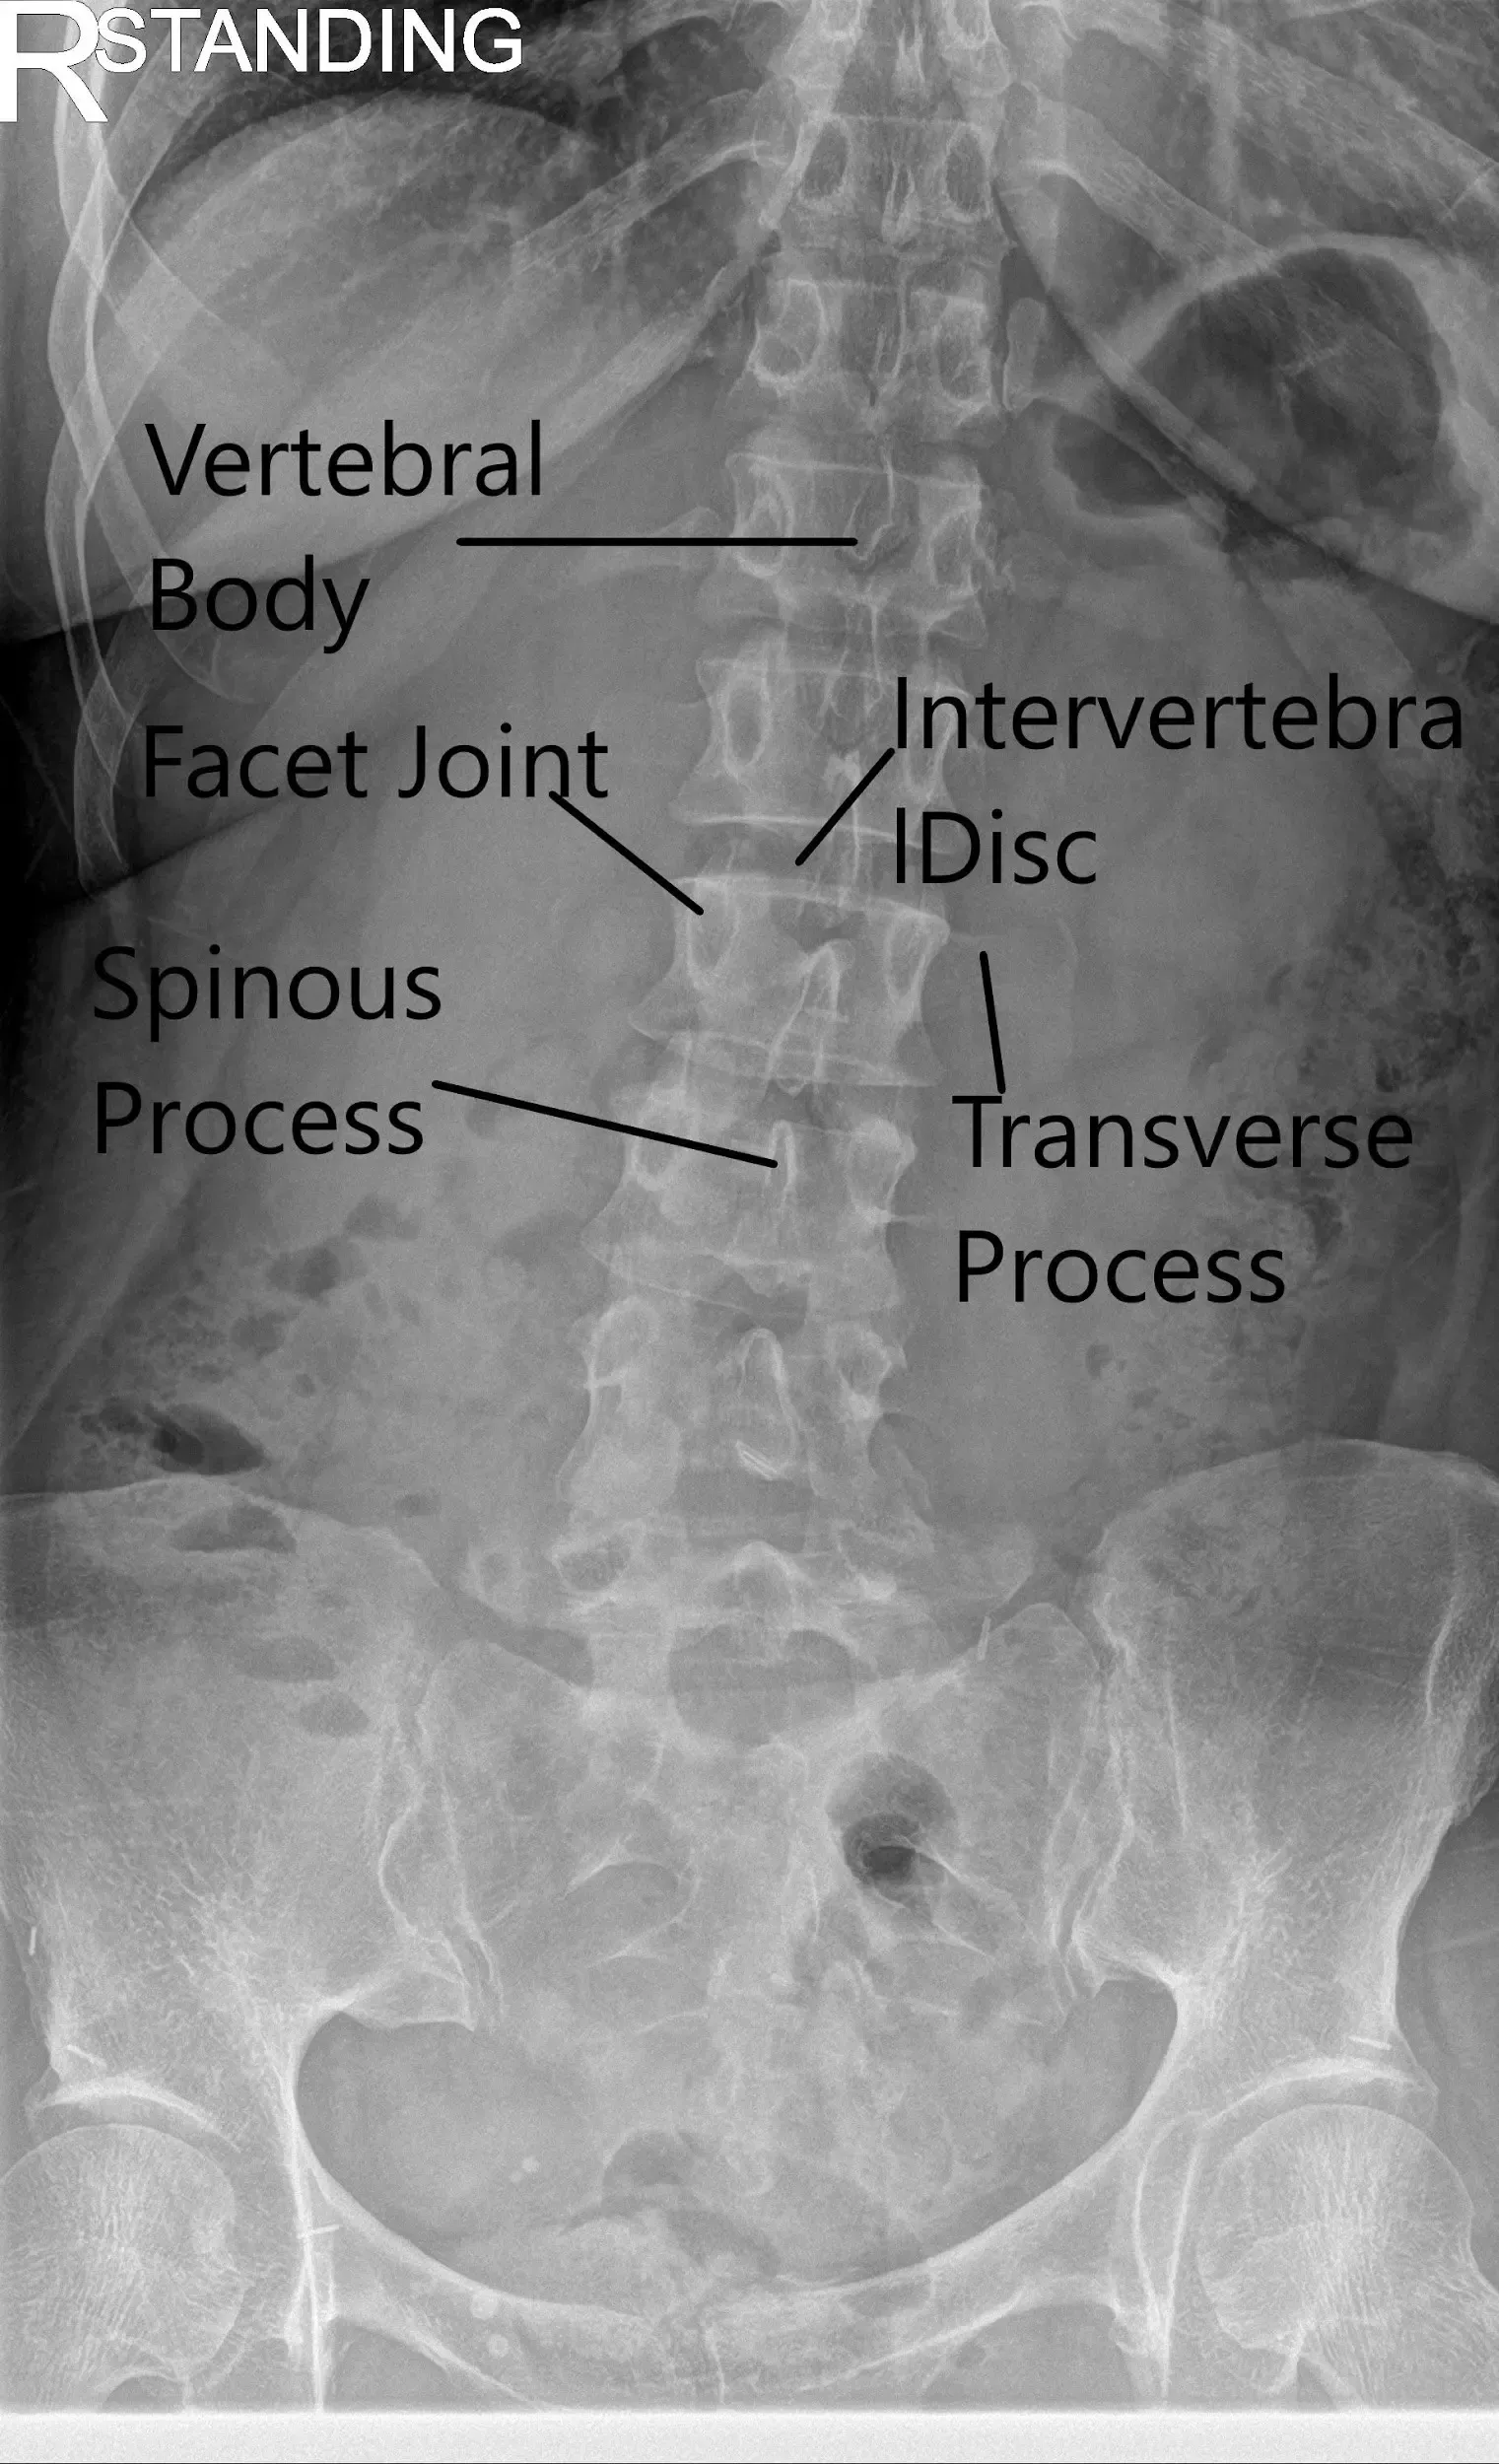

X-ray of the LS spine in AP and Lateral views showing degenerative changes.